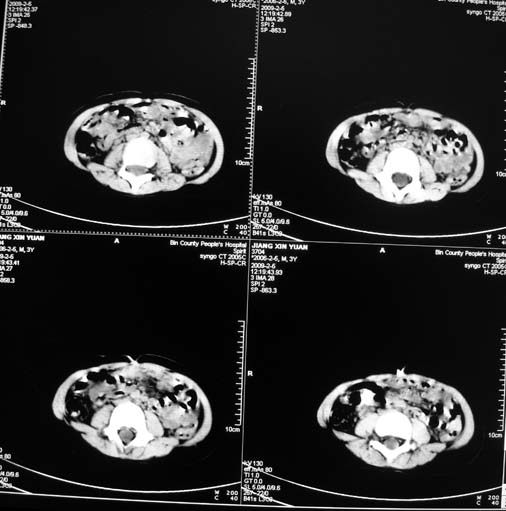

男,3岁,肾母细胞瘤术后,肝脏的低密度是什么?

胰尾下方见两枚囊形灶,肠管?病灶?左侧肾上腺区见团块状影,转移病灶?术后表现?建议与前片对比,肝脏病灶好像有牛眼表现,不除外转移,如果不增强,建议加做个b超,至少可分清其囊性或者实性,又便宜,免费自已给他弄一下也行,对诊断有帮助

左肾母细胞瘤术后:肝脏多发低密度灶,考虑转移可能性大。

左肾母细胞瘤术后:肝脏多发低密度灶,考虑转移可能.请结合临床及增强以及术前检查等